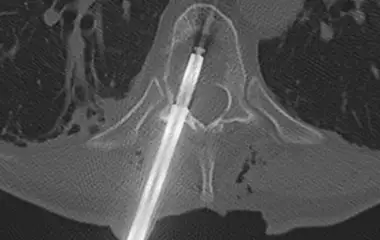

Sollte eine Operation nötig sein, können wir mit großer Routine minimalinvasive Eingriffe inkl. endoskopischer Technik aber auch invasivere Stabilisierungen der Wirbelsäule (Spondylodese) an Hals- Brust- und Lendenwirbelsäule von vorne, seitlich oder hinten durchführen. Die Eingriffe werden wenn möglich minimalinvasiv und mit Hilfe einer Neuronavigation sicher durchgeführt. Kleinere Eingriffe können wir in Kooperation mit der Wertachklinik Bobingen auch dort durchführen.